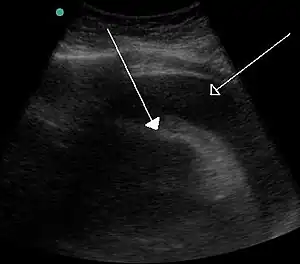

| A very large pericardial effusion resulting in tamponade as a result of bleeding from cancer as seen on ultrasound. Closed arrow - the heart; open arrow - the effusion | |